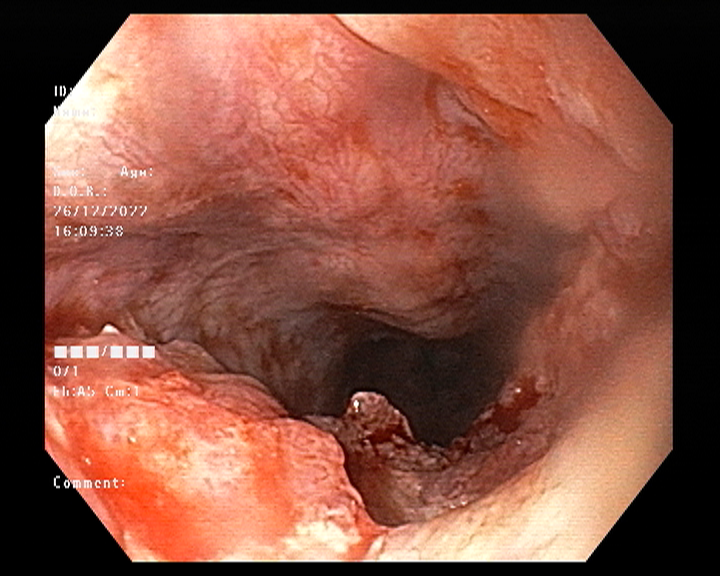

Endoscopy and colonoscopy are safe and accurate procedures used to directly examine the digestive tract and detect the root cause of chronic acidity, GERD, abdominal pain, bleeding, and bowel irregularities. These minimally invasive tests help identify ulcers, inflammation, infections, polyps, strictures, and early cancerous changes.

At Sapphire Gastroenterology Center, modern endoscopic equipment ensures precise diagnosis and, when required, therapeutic intervention during the same procedure. Based on findings, targeted treatment plans are created, including medication, diet guidance, and preventive strategies. Early diagnosis through endoscopy and colonoscopy plays a crucial role in preventing serious complications and improving long-term digestive health.